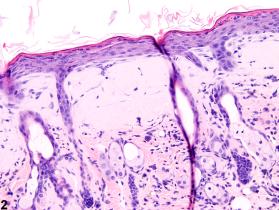

<p>Amyloid-accumulations of amorphous, eosinophilic, extracellular material in a female Swiss CD-1 mouse from a chronic study.</p>